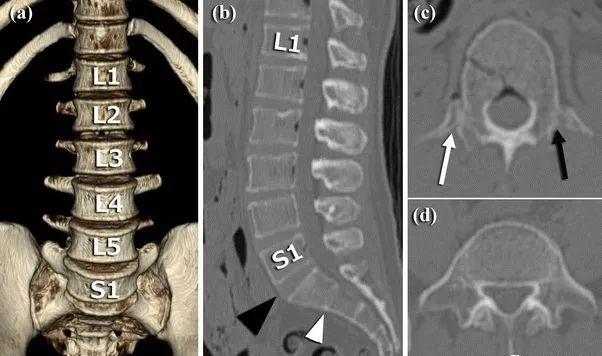

1984年,Castellvi提出LSTV分类系统将移行椎分为Ⅰ-Ⅳ型。

Ia型(单侧)和Ib型(双侧):横突肥大宽度超过19mm

IIa型(单侧)和IIb型(双侧):横突与骶骨相接触形成假关节

IIIa型(单侧)和IIIb型(双侧),横突与骶骨发生骨性融合

IV型:一侧横突与骶骨形成假关节另一侧形成骨性融合

目前,腰骶移行椎以Castellvi的分类方法最为常用。其主要根据横突形态及其与骶骨、髂骨是否融合或形成假关节而分为4型,Ⅰ、Ⅱ、Ⅲ型又根据单、双侧分为A、B两个亚型。

正常

I型:主要为腰5横突发育不良,横突宽度大于19mm,并将其分为两个亚型Ia(单侧横突发育不良)或Ib(双侧横突发育不良)

L5右侧横突肥大,为Ⅰa型

L5双侧横突肥大,为Ⅰb型

II型:表现为不完全的腰椎骶化,具有增宽的横突,并且和骶骨形成假关节,并将其分为两个亚型IIa(单侧关节形成)或IIb(双侧关节形成)

L5左侧横突肥大,假关节形成,为Ⅱa型

L5双侧横突肥大,假关节形成,为Ⅱb型

III型:单侧(IIIa)或双侧(IIIb)腰椎完全骶化,腰5横突与骶骨完全骨性融合

L5右侧横突肥大与骶骨发生骨性融合,为Ⅲa型

L5双侧横突与骶骨骨性融合,为Ⅲb型

IV型:一侧为II型即腰5横突与骶骨形成假关节,对侧为III型即腰5横突与骶骨形成骨性融合

IV型即混合型:L5双侧横突肥大,一侧与骶骨相接触为Ⅱ型表现,另一侧与骶骨形成骨性融合为Ⅲ型